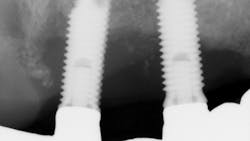

A recent retrospective study with a 10-year follow-up evaluated the long-term survival rates of natural teeth versus dental implants in 58 patients who were treated for chronic periodontal disease and then enrolled in periodontal maintenance programs.6 The study found that over 10 years, overall natural tooth loss (due to caries, endodontic reasons, and/or periodontal reasons) was .07 teeth per patient per year and .04 teeth per patient per year for periodontal reasons.

On the other hand, dental implant loss was 10 times higher, at .4 implants lost per patient per year. Ninety percent of the periodontally compromised teeth treated with active periodontal therapy (i.e., scaling/root planing, surgery, periodontal maintenance) survived over the 10-year period of the study. In addition, teeth designated with questionable prognoses at the baseline decreased by 1.9%, while teeth assigned with good prognoses increased by 3.6%. Overall implant survival in this study population was 90%, with 100% of implants surviving up to five years and then failing at a rate of 10.08% in the six- to 10-year range.

Another interesting finding in the study was that over the 10-year follow-up period, implants with a probing depth of six or greater and bone loss of 50% or greater increased 13.5% and 3.1%, respectively, while natural teeth decreased 8% and 10.7%, respectively. This would suggest that tooth prognosis increased over the study period, while implant prognosis decreased. Additionally, patients with probing depths of five or greater and/or full-mouth bleeding scores 25% or greater were at a significant increased risk for peri-implant disease, stressing the importance of controlling periodontal disease in patients who are candidates for implant therapy.8